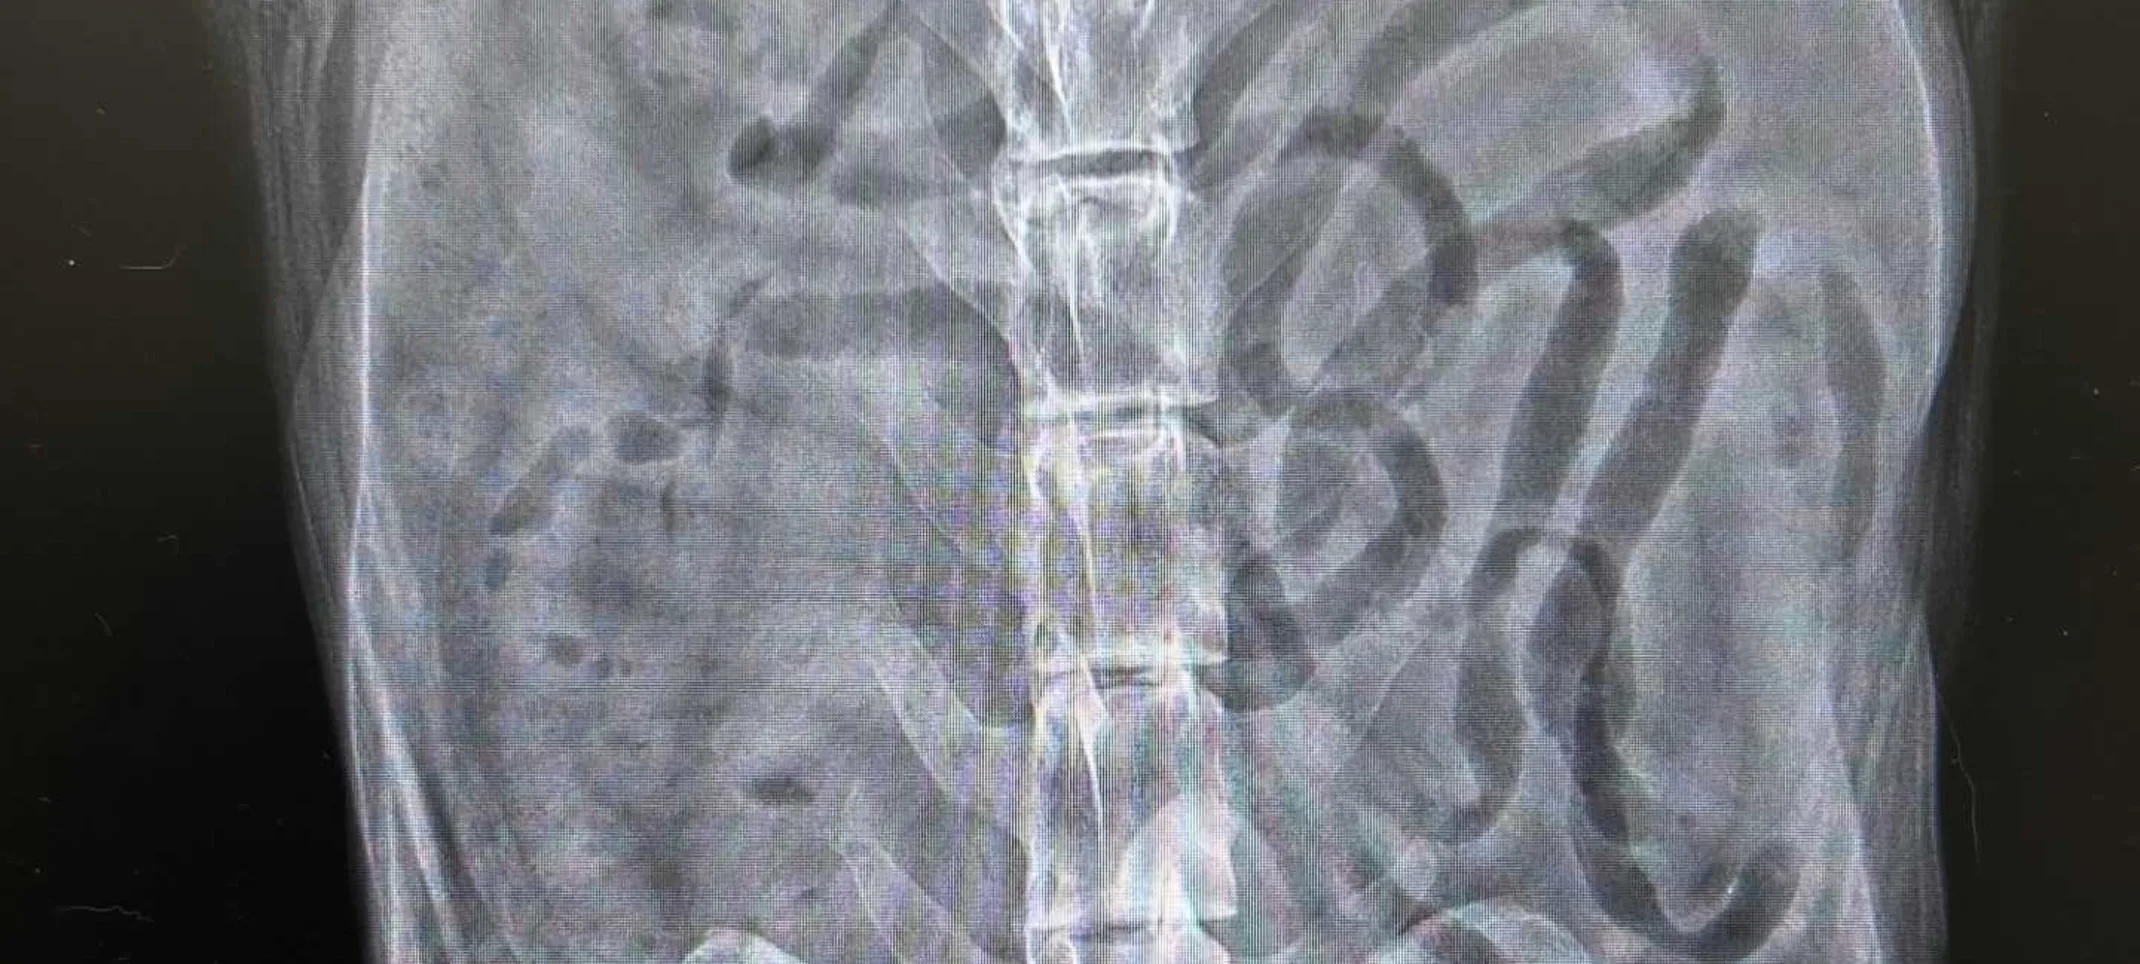

Our hospital has acquired a new state-of-the-art digital x-ray machine and offers advanced imaging services at our facility. Our radiologists can administer X-rays.

X-rays: This test can be used to accurately view an animal’s bone structure, bone fractures, and any foreign objects in the body.